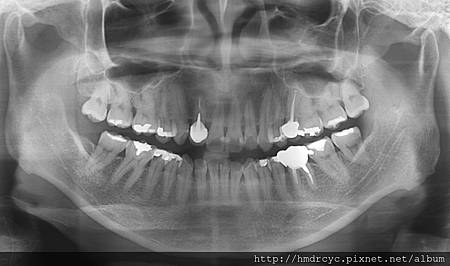

手術前確認X光片預先了解牙齒的位置與角度

全口片可以預先知道牙根型態與相關解剖位置

這個case是左營的C小姐 屬於複雜拔牙